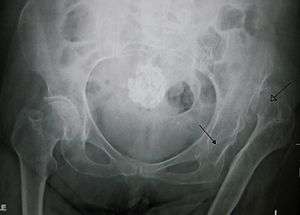

Dislocation of the hip is a common injury to the hip joint. Dislocation occurs when the ball–shaped head of the femur comes out of the cup–shaped acetabulum set in the pelvis. This may happen to a varying degree. A dislocated hip, much more common in females than in males, is a condition that can either be congenital or acquired.[1] Understanding the epidemiology, anatomy, difference between congenital and acquired, screening, treatments, and rehabilitation are all relevant to the topic.

The hip joint includes the articulation of the femoral head (of femur) and the acetabulum of the pelvis. In hip dislocation, the femoral head is dislodged from this socket. Posterior dislocation is the most prevalent, in which the femoral head lies posterior and superior to the acetabulum. This is most common when the femur is adducted and internally rotated. The opposite is true for the shoulder, where the most common dislocation occurs in the anterior and inferior directions.[1] The posterior side of the hip exhibits primarily hip extension, dealing with the muscles: gluteus maximus, hamstring muscles (biceps femoris, semitendinosus, semimembranosus), and the six deep external rotators (piriformis, obturator externus, obturator internus, gemellus superior, gemellus inferior, and quadrates femoris).[4]